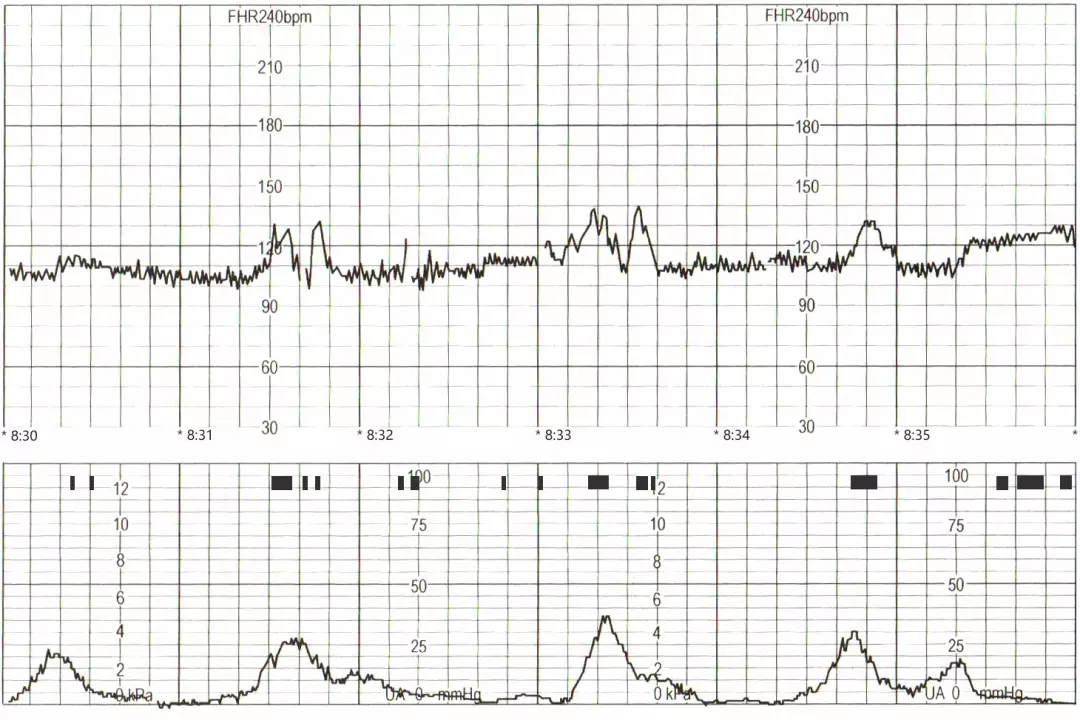

20分钟后,医生看了胎心监护图,确实很多宫缩,且强度还不小,虽然不是很规律。

临床上,胎心监护出现明显宫缩时,有些孕妇往往不自知,这和每个孕妇的感知能力不同有关。因此,如果有宫颈异常或孕中期出现过先兆早产的孕妈妈,最好能多留意宫缩情况,避免上述宫缩的影响因素,有条件者可以家里租一台含宫缩的胎心监护仪,每日监测。